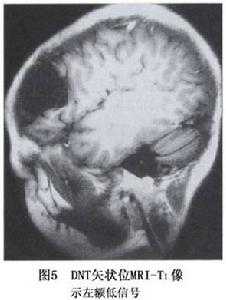

神經元腫瘤和神經元與神經膠質混合性腫瘤圖2

小腦發育不良性神經節細胞瘤(LDD)為小腦神經節細胞過度增生取代顆粒細胞與浦肯野細胞形成的錯構瘤樣病變至2003年文獻上共報導140例。本病由Lhermittle和Duclos在1920年報導,文獻上常稱之為LDD也稱之為小腦錯構瘤、浦肯野瘤或小腦良性肥大。本病可發生在任何年齡,以中青年居多,平均年齡為29歲和34歲,病程長,進展緩慢,主要症狀為顱壓增高、後組腦神經麻痹和小腦損害征。

小腦發育不良性神經節細胞瘤CT為低密度或低與等密度相交替的混雜密度可累及一側小腦半球,偶有鈣化,有輕度占位效應,可幕上腦室擴大及四腦室輕度移位。MRI可見小腦半球異常增大,腫瘤無明顯占位效應,T1像為沿小腦溝排列的低信號和等信號的分層結構T2像為高信號和等信號交錯形成“虎紋征”(圖2,3)。注藥無強化。